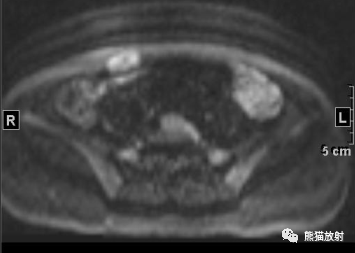

女41岁,腹壁肿物。

最后诊断: 韧带样纤维瘤

2、DTF形态较规则,以膨胀性生长为主,呈梭形或椭圆形,病灶沿着肌筋膜生长,矢状位显示本例病灶与肌肉长轴一致;

3、病灶边界多较清楚,也可浸润腹壁肌肉(筋膜尾征-较特征性表现)和皮下组织,或跨肌间隙,与腹膜、腹腔脏器粘连;

5、DTF信号特点及其不均匀性与病灶内组织学成分的比例和分布有关:细胞成分多的区域T2WI信号较高,胶原纤维多的区域T2WI信号较低;

6、病灶内各序列见条带状低信号影,无明显强化,病理为致密胶原纤维化和少细胞区,是 DTF较特征性的表现。